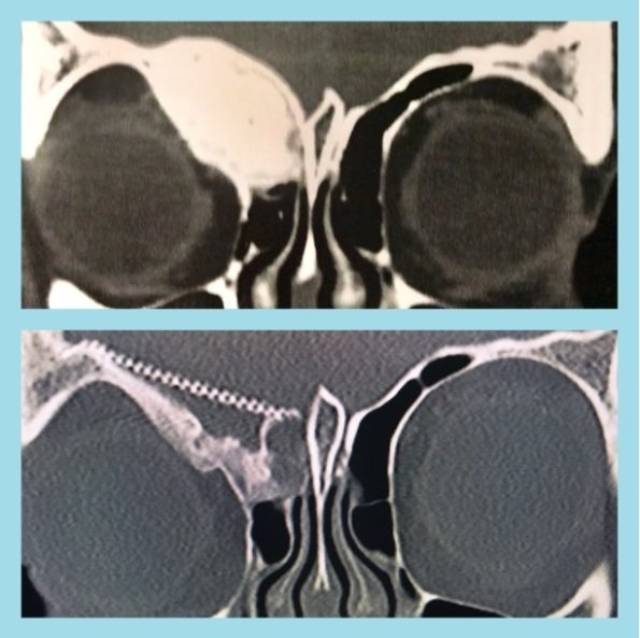

Tomografía y resonancia magnética

Pueda ayudar evaluar con exactitud la magnitud de la afectación ósea. La intensidad de señal en la resonancia magnética es moderadamente baja en T1, mientras en T2 es alta o media. Con gadolinio, la mayoría de las lesiones muestra un incremento central de contraste y algunos anillos periféricos.[5] En general, la intensidad de la señal depende de la cantidad de trabéculas óseas, colágeno, quistes y hemorragias. El clásico aspecto en la tomografía es de «vidrio esmerilado», que corresponde al hueso sano que rodea a la lesión.[5]